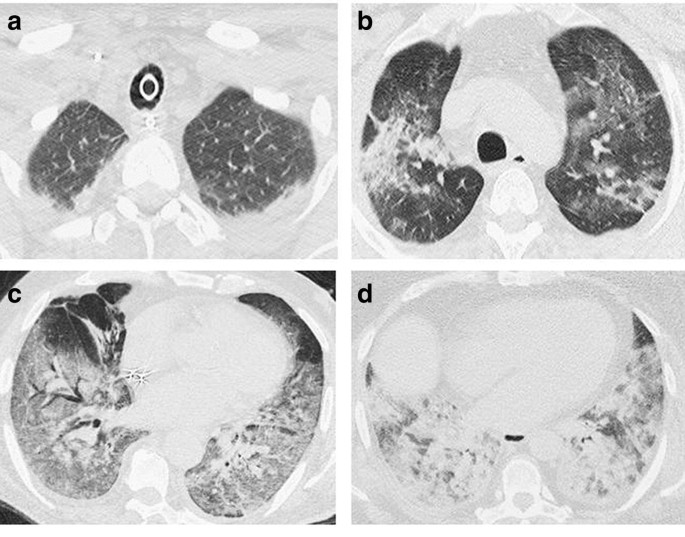

The frequency distribution of relevant vascular events detected using WB-CTA is depicted in Table 2A. Overall, they were reported in 71.4% (n = 30) of the study population, with a prevalence of 91% (n = 21) and 47% (n = 9) in ICU and non-ICU patients, respectively. Relevant vascular findings included both thrombotic/thromboembolic and hemorrhagic events. Pulmonary thromboembolism was the most frequent event in the whole population (35.7%), occurring in more than half of the ICU patients. It was associated with local or multi-focal detectable lung infarcts in 19% of cases (n = 8). A representative example of a massive PE occurring in a previously healthy young patient with no known risk factors is reported in Fig. 2. Ischemic infarction of other organs affected the gut, the spleen, the liver, the brain, and the kidneys with an increasing prevalence and a simultaneous ischemic occurrence in some patients, as shown in Fig. 3. Multi-focal venous thrombotic events were reported in 30.9% of the whole study population (n = 13). The majority of these events (11/13, 85%) occurred in the superior vena cava district with a frequency significantly higher in ICU patients, as detailed in Table 2A. Conversely, thrombosis of two main arteries (aorta and internal carotid artery) was reported in three cases with an overall prevalence of 7.1% and no differences between the two study groups. Active bleeding was recorded in 11.8% of patients (n = 5) with the involvement of skeletal muscles. Bleeding included both spontaneous (n = 2) and iatrogenic events (n = 3). A representative patient with multi-focal hemorrhages is shown in Fig. 4.

WB-CTA showing an extensive thrombotic filling defect within the aortic arch (a) and bilateral kidney infarction (b) in a 57-year-old no-ICU patient with acute chest pain and sudden onset of discoloration of the upper limbs. Thrombosis of the distal inferior cava and iliac veins (c) along with the concomitance of left iliac artery partial thrombotic occlusion in a 68-year-old ICU patient with acute onset of lower limb edema

Multi-site active bleeding in a 63-year-old ICU patient with sudden onset of dyspnea along with severe acute anemia. Arrows show contrast medium extravasation in the left carotid space (a), in the left rectus abdominis muscle (b), in the left psoas muscle and homolateral perirenal/posterior pararenal space (c), and the right iliac extra-peritoneal space (d)